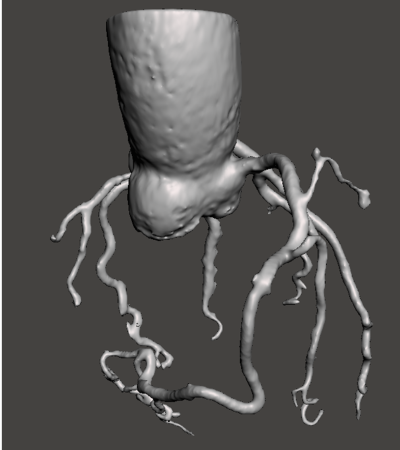

Les données sont obtenues par tomodensitométrie coronaire (CCTA), fournissant une visualisation détaillée de l’arbre coronaire en 3D.

Les artères sont segmentées puis converties en maillage 3D haute qualité, prêt pour les simulations numériques.